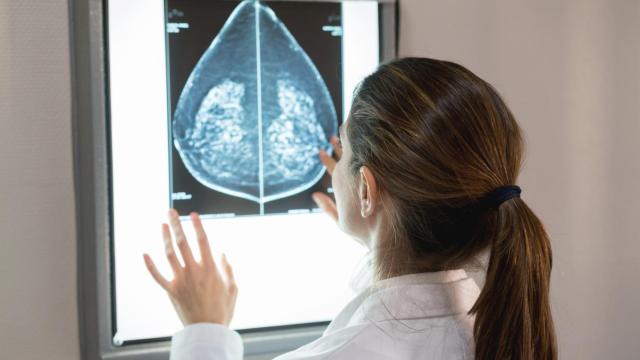

Cáncer de mama